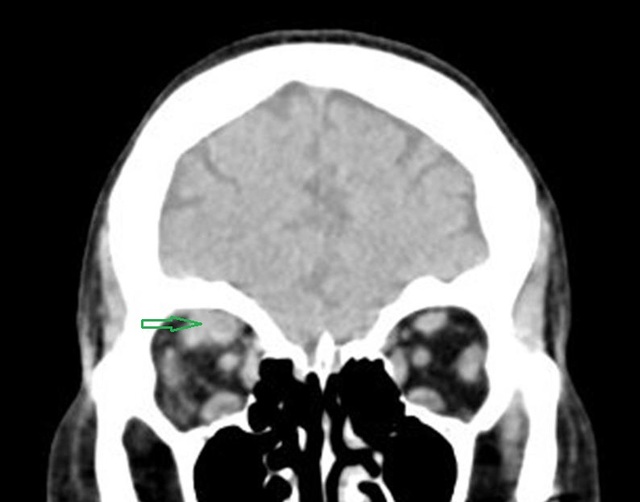

图 1 为平扫 CT,可见上直肌增粗(圈)